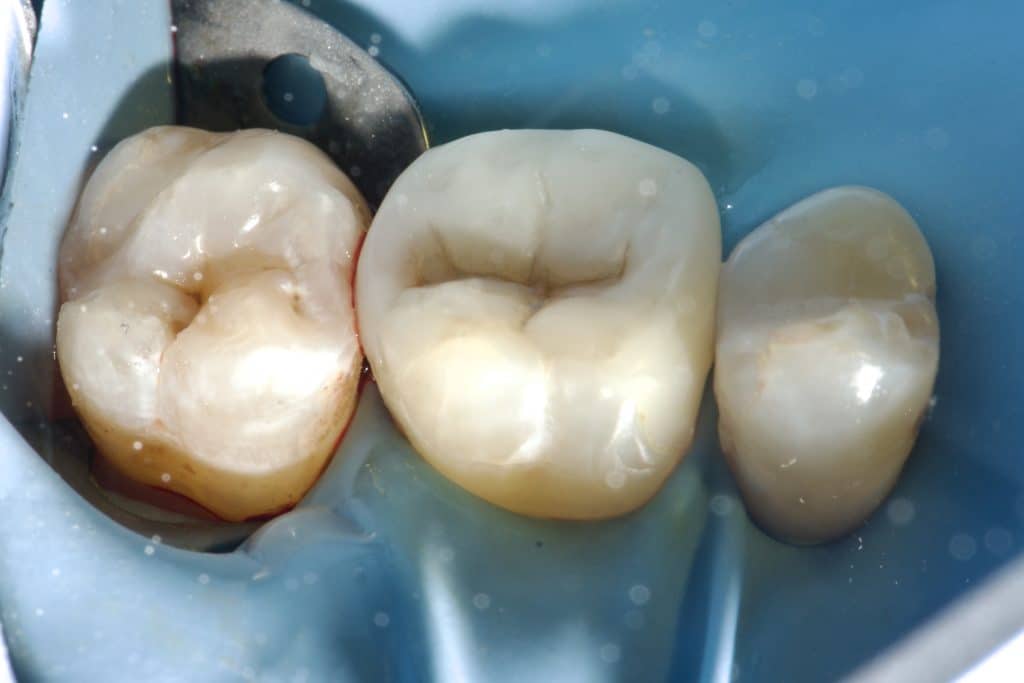

“Can a direct composite overlay function as effectively as an indirect lithium disilicate restoration? Composite restorations, once used as a long-term temporary solution for badly damaged molars, are now considered permanent. While the composite material remains the same, our understanding of its adhesive and physical properties has evolved. The procedure may be more time-consuming and require multiple stages in the same visit, depending entirely on the dentist’s skills.